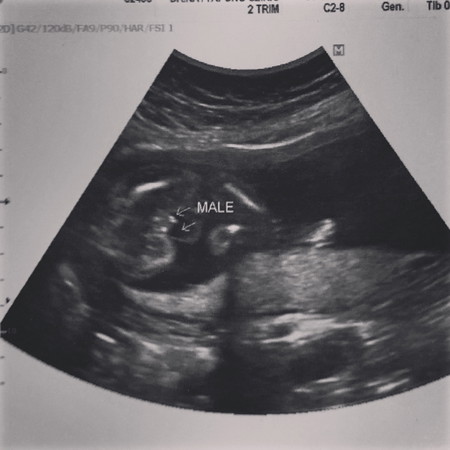

มีความสงสัย เพศลูก ??

ตอนแรกหมอบอกมีกลีบ,,พอซาวไปสักพัก บอกว่ามีจู๋ และหมอก็บอกว่าหมอเริ่มไม่แน่ใจ นี้ลุ้นสุดๆ เพราะอยากได้ ผู้ชาย มีลูกสาว 1 คนละ ค่ะ แม่ๆว่าเหมือนจู๋ มั้ยคะดูไม่ออกเลย ฮ่าๆๆๆ

กี่สัปดาห์แล้วคะ น่าจะจู๋ เห็นแหลมๆ

น่าจะผช.จ้า หมอขึ้นเพศให้แล้ว

น่าจะผู้ชายค่ะ

เป็น ผู้ชาย นี้ดีใจสุดๆไปเลยค่ะ เพราะมีลูกสาว 1 คนละคะ จะได้ปิดอู่ 😊